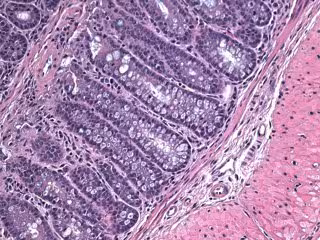

Célula de un ratón

JOHN DOWLING, JEFFERSON